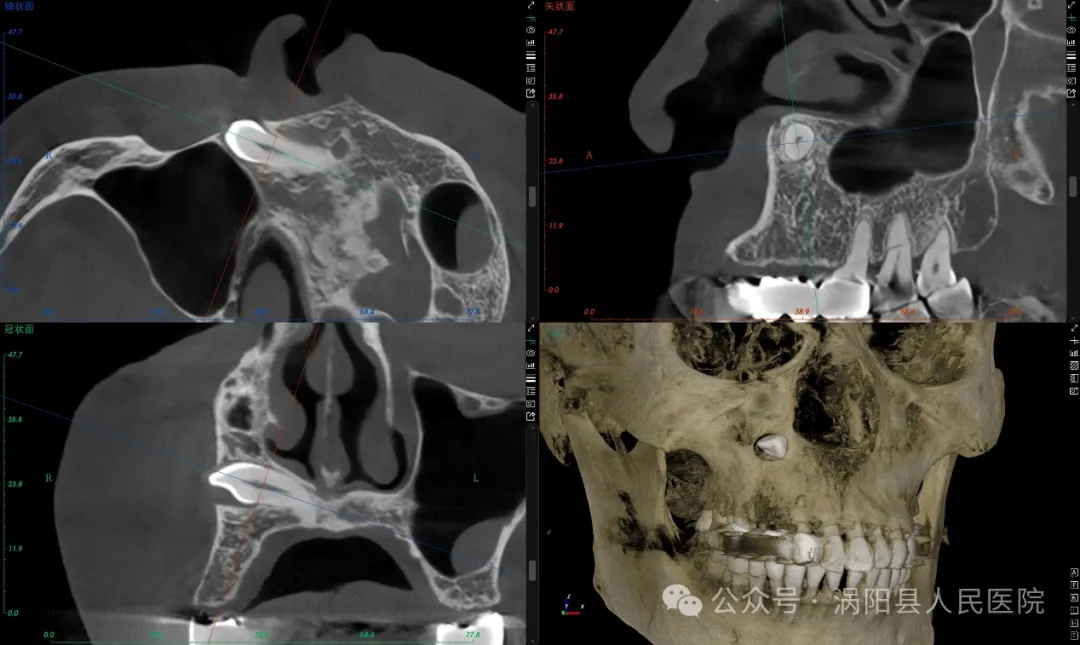

于女士近几个月来,右侧脸部反复肿痛不适,对日常生活造成了比较大的影响,在外院拍片发现右侧眼眶下方有一颗埋伏阻生尖牙而且周围的牙囊明显增生。为了解决这颗“离家出走”的埋伏牙,于女士辗转多家医院就医,但医生纷纷表示手术难度大,有的直接推脱,有的说需要在面部做切口,有的说必须全麻手术,这让她忐忑不安,心生恐惧。

经过完善的术前准备,缜密地分析,并与患者及其家属讨论后,最终决定在门诊局麻下经口内入路操作。7月12日,杨华一医生在口腔科荆秀侠护士长的高效配合下,微创分离显露埋伏牙后见周围的牙囊和骨质明显发炎增生,借助超声骨刀和口腔外科动力系统进行精准、微创的增隙分牙,迅速拔除埋伏牙并刮净周围增生的牙囊及炎性组织。